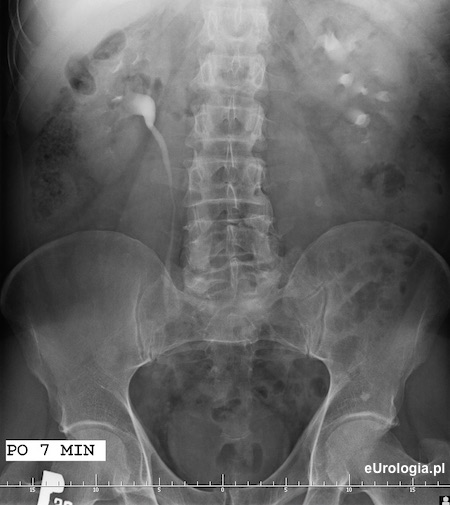

Po 7 minutach uzyskano zakontrastowanie układu kielichowo-miedniczkowo-moczowodowego prawej nerki i górnego odcinka prawego moczowodu. Ślad zakontrastowanego moczu w obrębie UKM nerki po stronie lewej.